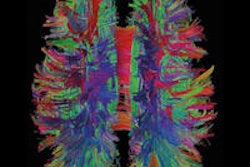

The technique was developed through the Human Connectome Project, a $30 million, five-year effort to map the brain's connectivity. The project is led by Washington University and the University of Minnesota.